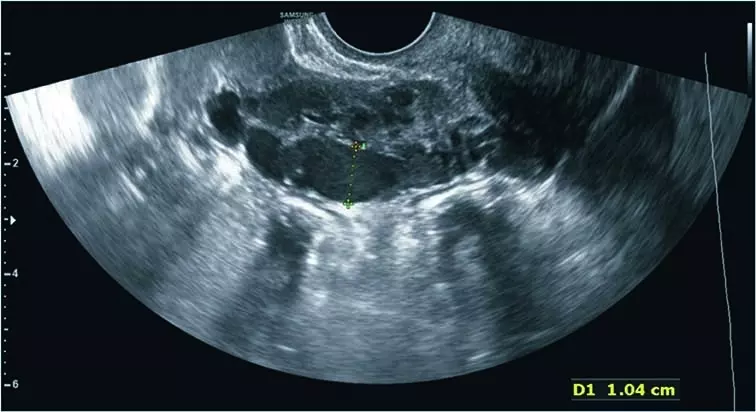

Po ok. 3 miesiącach występowania dolegliwości pacjentka zgłosiła się do lekarza rodzinnego, który po wykonaniu badań podstawowych [morfologia, CRP (ang. C reactive protein), parametry życiowe – wszystkie w normie], ze względu na opisywany związek dolegliwości z cyklem miesiączkowym i współżyciem zalecił konsultację ginekologiczną. W badaniu dwuręcznym stwierdzono niewielką tkliwość przydatków i macicy, we wziernikach obecność obfitej, niezapalnej wydzieliny w pochwie, pH 4.0. Lekarz ginekolog wykonał również ultrasonograficzne (USG) badanie przezpochwowe, nie stwierdzając nieprawidłowości. Podejrzewając zapalenie przydatków, zalecił antybiotykoterapię i dalsze konsultacje w przypadku braku poprawy. Antybiotykoterapia nie zmniejszyła dolegliwości bólowych, pacjentka była również konsultowana przez chirurgów i gastrologów, wykonano USG jamy brzusznej oraz komplet badań biochemicznych, nie zdiagnozowano przyczyny bólu. W czasie procesu diagnostycznego podejmowano próby leczenia empirycznego za pomocą doustnej antykoncepcji hormonalnej, leków rozkurczowych, niesterydowych leków przeciwzapalnych i antybiotyków – bez pozytywnego efektu. W trakcie kolejnej konsultacji ginekologicznej, ze względu na podejrzenie endometriozy, pacjentce zaproponowano laparoskopię diagnostyczną, w trakcie której nie stwierdzono nieprawidłowości. Wobec niestwierdzenia patologii mogącej tłumaczyć objawy poinformowano pacjentkę o możliwości rozważenia histerektomii z przydatkami bądź próby rozważenia zaakceptowania dolegliwości. Ostatecznie, po ok. 1,5 roku od wystąpienia pierwszych objawów, pacjentka trafiła na konsultację do III Kliniki Ginekologii. W trakcie ponownego przezpochwowego badania USG uwagę zwróciły następujące znaleziska: liczne poszerzone naczynia żylne w obrębie myometrium (ryc. 1) oraz poszerzone naczynie żylne w okolicy lewych przydatków – żyła jajnikowa lewa (ryc. 2). Po uciśnięciu sondą pacjentka podawała jedynie nieznaczne dolegliwości w okolicy lewego jajnika, natomiast bardzo żywo reagowała bólowo przy ucisku okolicy poszerzonego naczynia. W badaniu dopplerowskim w poszerzonej żyle jajnikowej stwierdzono nieprawidłowy, wahadłowy przepływ (ryc. 3). Na podstawie obrazu USG wysunięto podejrzenie zespołu PCS. W kolejnym etapie diagnostyki wykonano badanie rezonansu magnetycznego z opcją naczyniową, w którym stwierdzono znaczne poszerzenie splotów żylnych przymacicz oraz żyły jajnikowej lewej, potwierdzając rozpoznanie PCS.

Ryc. 1. W przezpochwowym badaniu USG w obrębie myometrium stwierdzono obecność licznych poszerzonych żył łukowatych (echoujemne obszary)